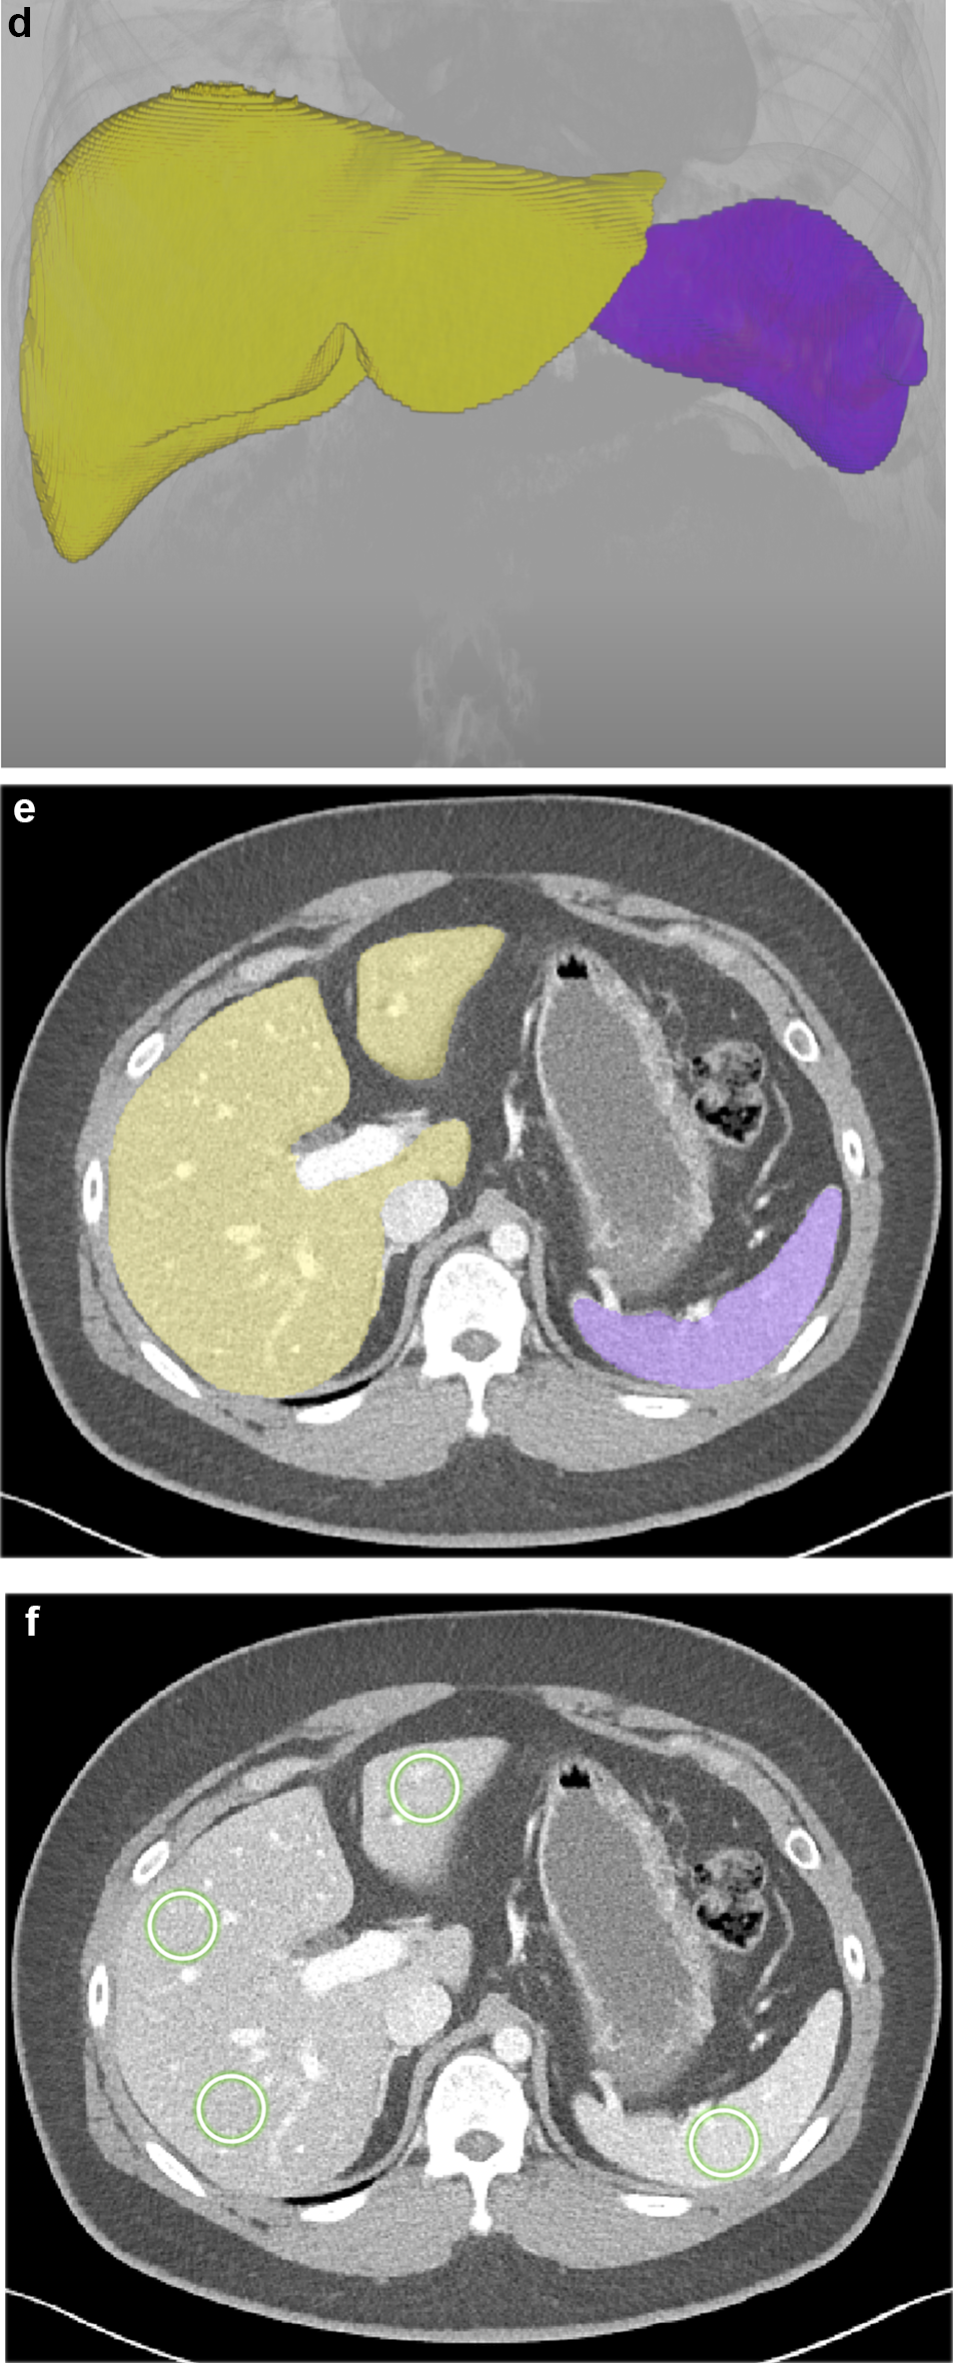

Fig. 2

Liver CT scan of a 35-year-old man with chronic hepatitis B and severe steatosis, with a controlled attenuation parameter value of 312. Fully automated 3D segmentation of the liver and spleen was performed on pre-contrast (a–c) and post-contrast images (d–f). Based on the 3D organ segmentation (a, d: 3D volume rendering images; b, e: axial images showing liver and spleen segmentation), the volumetric mean CT attenuation values were automatically measured as follows: L_pre = 31.1 HU, S_pre = 39.1 HU; L_post = 116.4 HU, S_post = 143.2 HU. Accordingly, L-S_pre = -8.0 HU and L-S_post = -26.8 HU, indicating severe steatosis. CT attenuation measurements using the 2D region-of-interest method on axial sections (c, f) were 35.6 HU and 42.2 HU for the liver and spleen on the pre-contrast image, and 115.8 HU and 154.5 HU on the post-contrast image. L = mean CT attenuation values of the liver; S = mean CT attenuation values of the spleen; L-S = L minus S.